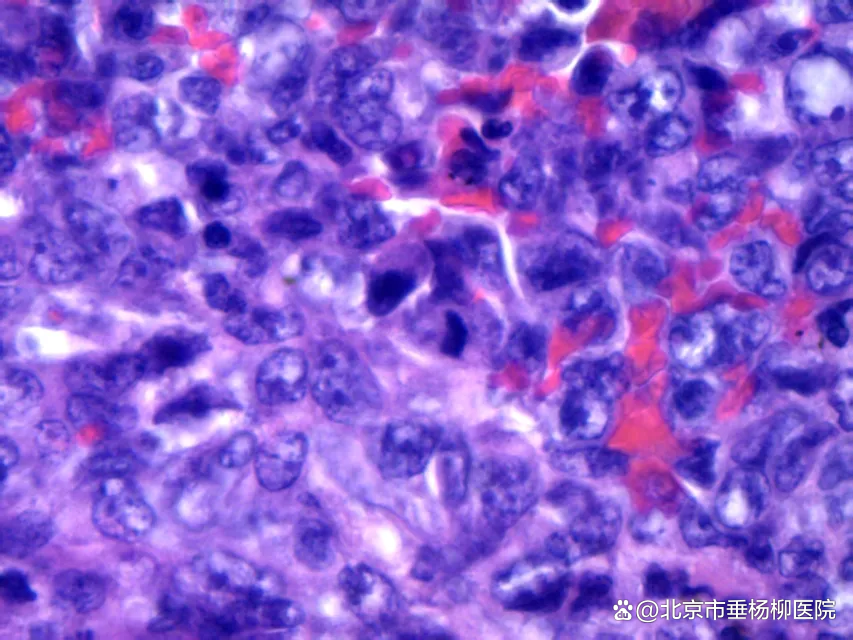

细胞沉渣石蜡包埋HE切片:血性背景中可见大量恶性肿瘤细胞,粘附性差,核形不规则,可见泡状核,部分胞浆丰富,核分裂象易见。